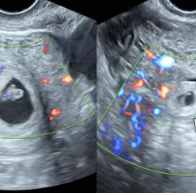

李女士宫内外双孕囊所在位置。

患者李女士因生育难题接受试管婴儿技术,成功妊娠。在一次常规早孕期超声检查中,该院超声科副主任、主任医师张军辉探及宫腔内孕囊及胎芽,胎心搏动有力。在问诊中得知李女士移植了两枚胚胎后,张军辉对双侧附件区进行细致扫查,于右侧附件区发现孕囊样结构,经多角度、多切面反复探查,精准诊断为“宫内外复合妊娠”。